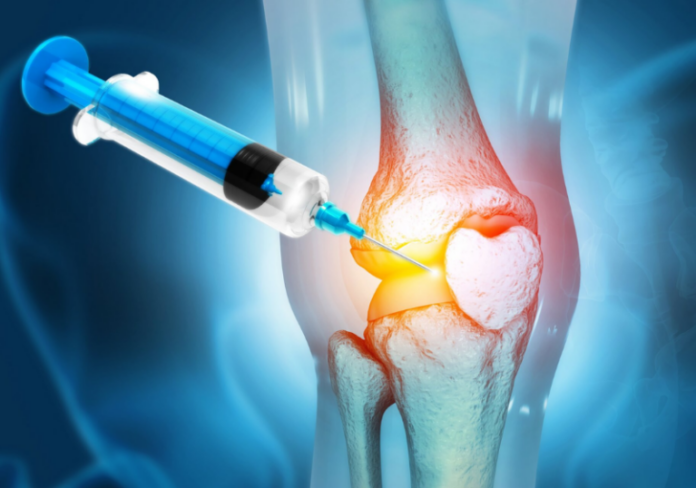

Esta injeção antienvelhecimento utiliza avanços da medicina regenerativa para estimular o próprio corpo a reconstruir o tecido perdido. A abordagem foca na causa raiz: o envelhecimento e a senescência das células da cartilagem (condrócitos). Ao restaurar a função juvenil dessas células, a cartilagem começa a se regenerar, preenchendo as áreas desgastadas. O prazo de 6 meses para uma regeneração significativa representa um salto quântico na velocidade de recuperação articular. Imagine voltar a caminhar, subir escadas, praticar esportes ou simplesmente levantar da cadeira sem dor. Se você ou alguém que você ama sofre com artrite no joelho, compartilhe esta esperança. O futuro da saúde articular é regenerativo, não apenas paliativo. O “impossível” está se tornando “realidade” agora.